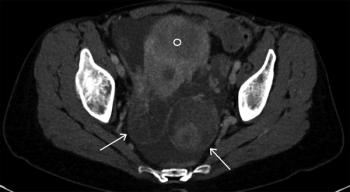

A 43-year-old man presents with a mass lesion in the pelvis, and a biopsy is performed. What is your diagnosis?